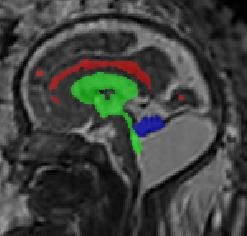

Limiting failures of machine learning systems is of paramount importance for safety-critical applications. In order to improve the robustness of machine learning systems, Distributionally Robust Optimization (DRO) has been proposed as a generalization of Empirical Risk Minimization (ERM). However, its use in deep learning has been severely restricted due to the relative inefficiency of the optimizers available for DRO in comparison to the wide-spread variants of Stochastic Gradient Descent (SGD) optimizers for ERM. We propose SGD with hardness weighted sampling, a principled and efficient optimization method for DRO in machine learning that is particularly suited in the context of deep learning. Similar to a hard example mining strategy in practice, the proposed algorithm is straightforward to implement and computationally as efficient as SGD-based optimizers used for deep learning, requiring minimal overhead computation. In contrast to typical ad hoc hard mining approaches, we prove the convergence of our DRO algorithm for over-parameterized deep learning networks with ReLU activation and a finite number of layers and parameters. Our experiments on fetal brain 3D MRI segmentation and brain tumor segmentation in MRI demonstrate the feasibility and the usefulness of our approach. Using our hardness weighted sampling for training a state-of-the-art deep learning pipeline leads to improved robustness to anatomical variabilities in automatic fetal brain 3D MRI segmentation using deep learning and to improved robustness to the image protocol variations in brain tumor segmentation. Our code is available at https://github.com/LucasFidon/HardnessWeightedSampler.